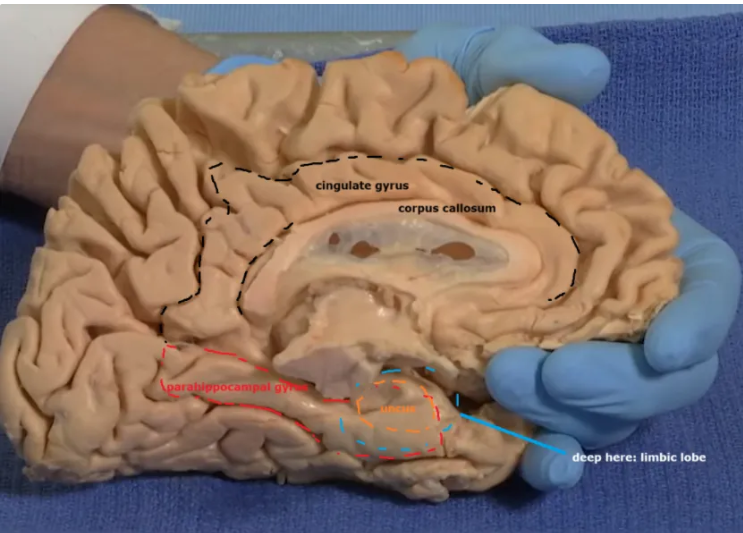

Overlaying the green cingulate and parahippocampal gyri with the purple hippocampus highlights the limbic lobe. Yellow = fornix. Brownish pink = hypothalamus